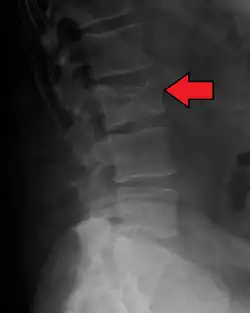

Bone pain affects almost 70% of people with multiple myeloma and is one of the most common symptoms.[2]: 653 [23] Myeloma bone pain usually involves the spine and ribs and worsens with activity. Persistent, localized pain may indicate a pathological bone fracture. Involvement of the vertebrae may lead to spinal cord compression or kyphosis. Myeloma bone disease is due to the overexpression of receptor activator for nuclear factor κ B ligand (RANKL) by bone marrow stroma. RANKL activates osteoclasts, which resorb bone. The resultant bone lesions are lytic (cause breakdown) in nature. They are best seen in plain radiographs, which may show "punched-out" resorptive lesions (including the "raindrop" appearance of the skull on radiography). The breakdown of bone also leads to the release of calcium ions into the blood, leading to hypercalcemia and its associated symptoms.[24]

The diagnostic examination of a person with suspected multiple myeloma typically includes a skeletal survey. This is a series of X-rays of the skull, axial skeleton, and proximal long bones. Myeloma activity sometimes appears as "lytic lesions" (with local disappearance of normal bone due to resorption) or as "punched-out lesions" on the skull X-ray ("raindrop skull"). Lesions may also be sclerotic, which is seen as radiodense.[76] Overall, the radiodensity of myeloma is between −30 and 120 Hounsfield units (HU).[77] Magnetic resonance imaging is more sensitive than simple X-rays in the detection of lytic lesions. An MRI may supersede a skeletal survey, especially when vertebral disease is suspected. Occasionally, a CT scan is performed to measure the size of soft-tissue plasmacytomas. Nuclear Medicine Bone scans are typically not of any additional value in the workup of people with myeloma (no new bone formation; lytic lesions not well visualized on nuclear bone scan).

Pathological fracture of the lumbar spine due to multiple myeloma -